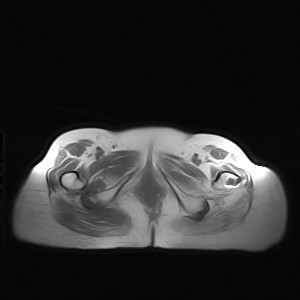

标题: MRI2691:读片病例2

我帮传的没看到病史!!!

图像太差了 1、右侧臀肌旁脓肿? 建议增强 2、左侧股骨头坏死并半脱位

1、左侧股骨头坏死并髋关节半脱位;

2、右侧臀肌感染,(可能褥疮所致)